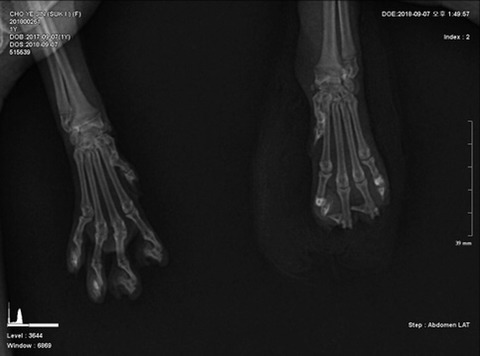

์™ผ์ชฝ์ด ์„์ด ์ •์ƒ๋ฐœ์ด๊ณ  ์˜ค๋ฅธ์ชฝ์ด ์„์ด ๋ฆฐ์น˜๋‹นํ•œ ๋ฐœ์ด์•ผ

๊ณ ์–‘์ด ๋ฐœ์€ ๋์ด ๋‘๋งˆ๋””+๋ฐœํ†ฑ ์ด์–ด์•ผํ•˜๋Š”๋ฐ ์„์ด๋Š” ์˜ค๋ฅธ์ชฝ๋ฐœ 3,4๋ฒˆ์งธ ๋ฐœ๊ฐ€๋ฝ ์ฒซ๋งˆ๋””๊ฐ€ ์ž˜๋ ธ์–ด

๊ณ ์–‘์ด๋“ค์€ ๋ฐœ๋ฐ”๋‹ฅ๋ณด๋‹ค๋Š” ๋ฐœ๊ฐ€๋ฝ์œผ๋กœ ๊ฑธ์–ด๋‹ค๋‹ˆ๊ธฐ ๋•Œ๋ฌธ์— ์„ ์ƒ๋‹˜๊ป˜์„œ๋Š” ์ตœ๋Œ€ํ•œ ๋„“์€ ๋ถ€๋ถ„์„ ์‚ด๋ฆฌ๋ ค๊ณ  ์ฒซ๋ฒˆ์งธ ๋งˆ๋””๋งŒ ์ œ๊ฑฐํ•˜๋ ค๊ณ  ํ•˜์…จ๋Š”๋ฐ ํ”ผ๋ถ€ ๊ดด์‚ฌ๊ฐ€ ์ƒ๊ฐ๋ณด๋‹ค ๋งŽ์ด ์ง„ํ–‰๋œ์ƒํƒœ๋ผ ๊ฒฐ๊ตญ ๋‘๋ฒˆ์งธ ๋งˆ๋””๊นŒ์ง€ ์ ˆ๋‹จ์„ ํ•˜๊ฒŒ๋์–ด